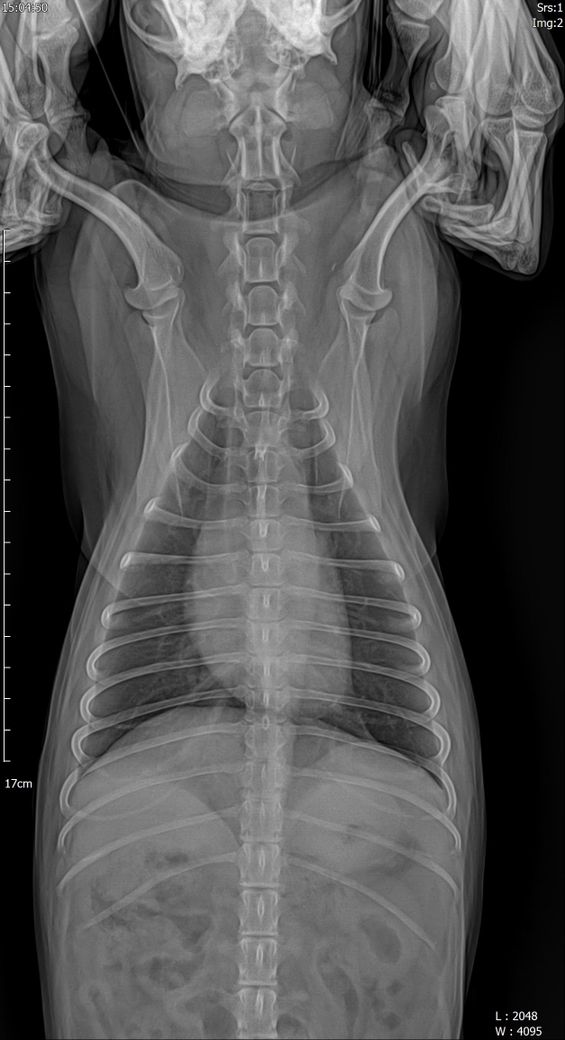

강아지 폐 기관지 엑스레이 좀 봐주세요

안녕하세요 어디서는 섬유화가 진행중이라고하고 3일뒤 다른병원가서 다시찍으니 만성기관지염이라고하네요 엑스레이 좀 봐주세요 ㅠㅠ기침은 하루에 켁켁켁카악 이걸 한번으로치면 3번정도는 해요 기본 한두번은 항상하구요

방사선 검사에서 초기 폐섬유화증은 만성 기관지염과 동일한 소견을 보입니다. 그래서 실제 조직검사를 하기 전까즈는 폐섬유화증고 만성기관지염은 방사선 검사를 통해 감별할 수 없습니다.

또한 만성 기관지염이 진행되면 시간이 흐르면 폐섬유화증이 동반되기 때문에 엄격하게 이 둘을 구분하는것은 초기인 경우 큰 의미는 없습니다.

또한 폐 섬유화증이 진행하여 임상증상이 발현하는 빈도는 매우 낮고 만성기관지염은 이보다 훨씬 잦게 나타나는 현상으로 둘을 구분하기보다 만성 기관지염으로 가정을 하고 치료하는게 옳은 선택입니다.

첨부한 사진에서 세기관지벽의 침윤 양상과 함께 무정형의 간질성 침윤이 동반되어 있기 때문에 일차적으로 만성 기관지염이 있을 가능성이 매우 높고, 이 사항이 충분히 관리되지 않으면 향후 폐섬유화증으로 진행될(혹은 일부 진행된 상황) 가능성을 고려해야 하니 두 동물병원의 소견이 모두 맞다고 볼 수 있습니다.